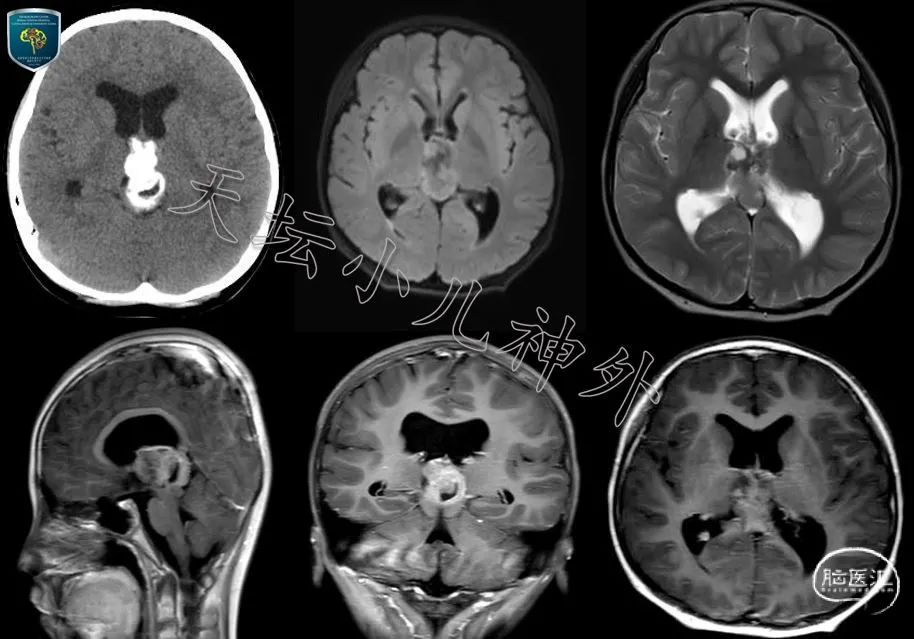

病例分析:室管膜瘤诊断要点

图片尺寸640x874